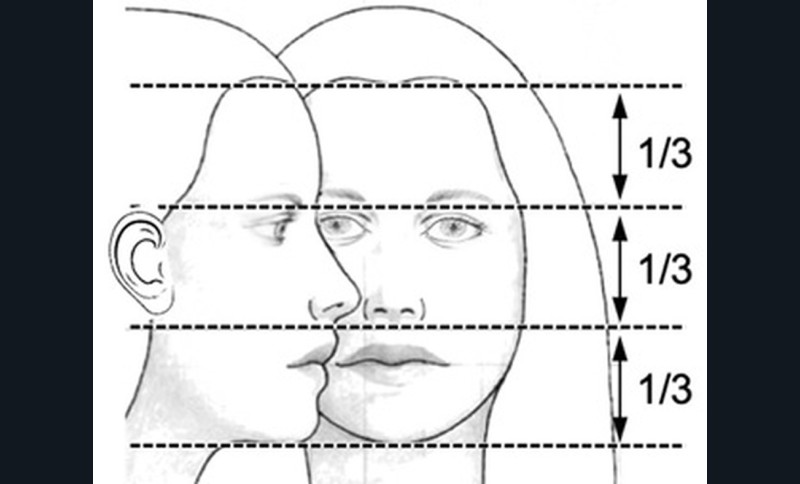

L’examen clinique orthodontique débute par un examen exobuccal de face et de profil qui permet à l’orthodontiste d’identifier certains signes d’appel du Sahos [4]. L’examen de face apprécie la forme globale du visage, la typologie et la symétrie faciale (fig. 5). Des signes caractéristiques sont souvent rapportés chez les enfants suspectés de Sahos : incompétence labiale au repos, hypotonie de la lèvre supérieure avec un angle naso-labial augmenté, visage allongé, orifices narinaires étroits et pincés et présence de cernes (fig. 6a) [5]. Ce sont des indicateurs indirects d’une obstruction ou d’un rétrécissement nasal et d’une ventilation buccale [5-6].

L’examen de profil apprécie les rapports maxillo-mandibulaires et la convexité du visage dans le sens antéropostérieur. Chez les enfants apnéiques, on note généralement la présence d’un profil convexe rétrusif avec un menton en retrait, associé à des dépôts graisseux si l’enfant est en surpoids. Une hypotonie de la lèvre supérieure, qui se traduit par un angle naso-labial ouvert, signe d’un hypo-développement maxillaire, est souvent présente [7]. Enfin, on observe parfois une contraction du muscle mentonnier associée à une occlusion labiale forcée (fig. 6b).